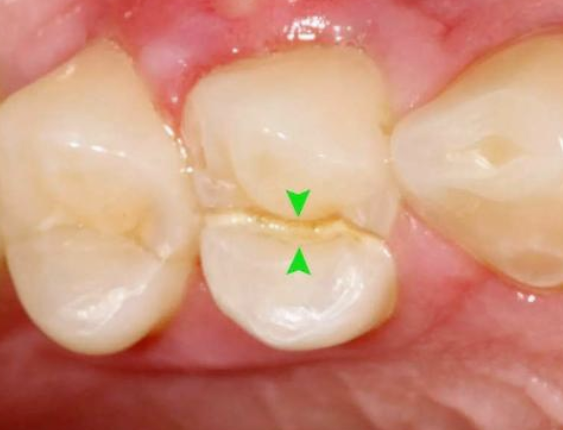

调𬌗的具体方法,只需四步!(附检查方法)